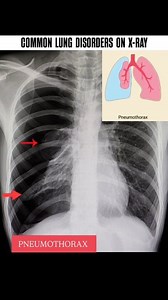

232K views · 1.7K reactions | Common lung disorders on x-Ray.. 贈 #radiology_technique #viralreels #reelsinstagram #medicogirl #mbbsabroad #radiology #xray #reels #radiologist #mbbs #mbbsstudent #radiologia #LungHealth #PulmonaryCare #pulmonology #pulmonologist | Diwakar Patel | Facebook

Facebook

Diwakar Patel

已浏览 6.3万 次

2 周前